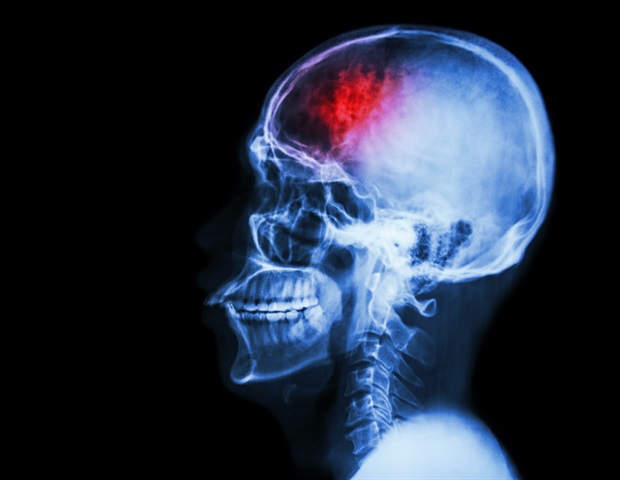

Το παραλήρημα, μια κατάσταση που συχνά παρατηρείται σε ασθενείς σε κρίσιμη κατάσταση μετά από ενδοεγκεφαλική αιμορραγία (ICH), χαρακτηρίζεται από οξείες διαταραχές στην προσοχή, τη συνείδηση και τη γνωστική λειτουργία. Παρά την κλινική του σημασία, οι μηχανισμοί που το διέπουν παραμένουν σε μεγάλο βαθμό ανεξερεύνητοι. Σκοπός της παρούσας μελέτης ήταν να εξετάσει τη λειτουργική σύνδεση του ανιόντος δικτύου ενεργοποίησης (ARAS) σε ασθενείς με παραλήρημα και αιμορραγία στη βασική γάγγλια, καθώς και να εντοπίσει πιθανούς βιοδείκτες για την πρόβλεψη της εμφάνισης του παραληρήματος.

Σημαντική διαταραχή στη σύνδεση μεταξύ των πυρήνων του ARAS στο εγκεφαλικό στέλεχος και του αριστερού παραϊπποκαμπικού φλοιού παρατηρήθηκε στους ασθενείς με παραλήρημα. Η δύναμη της σύνδεσης μεταξύ αυτών των περιοχών αποδείχθηκε αξιόπιστος προγνωστικός δείκτης για την εμφάνιση του παραληρήματος, με περιοχή κάτω από την καμπύλη 0.893, υποδεικνύοντας υψηλή προγνωστική ακρίβεια.

Η διαταραχή της σύνδεσης μεταξύ του εγκεφαλικού στελέχους και του παραϊπποκαμπικού φλοιού μπορεί να υποδηλώνει τις παθογενετικές διαδικασίες πίσω από το παραλήρημα. Η αντίστοιχη δύναμη της σύνδεσης θα μπορούσε να χρησιμεύσει ως αποτελεσματικός βιοδείκτης για την πρόβλεψη της εμφάνισης του παραληρήματος. Η αποκατάσταση της φυσιολογικής σύνδεσης μεταξύ αυτών των περιοχών ενδέχεται να αποτελεί στρατηγική για την πρώιμη αναστροφή του παραληρήματος και αποτελεί κεντρικό σημείο για μελλοντική έρευνα.